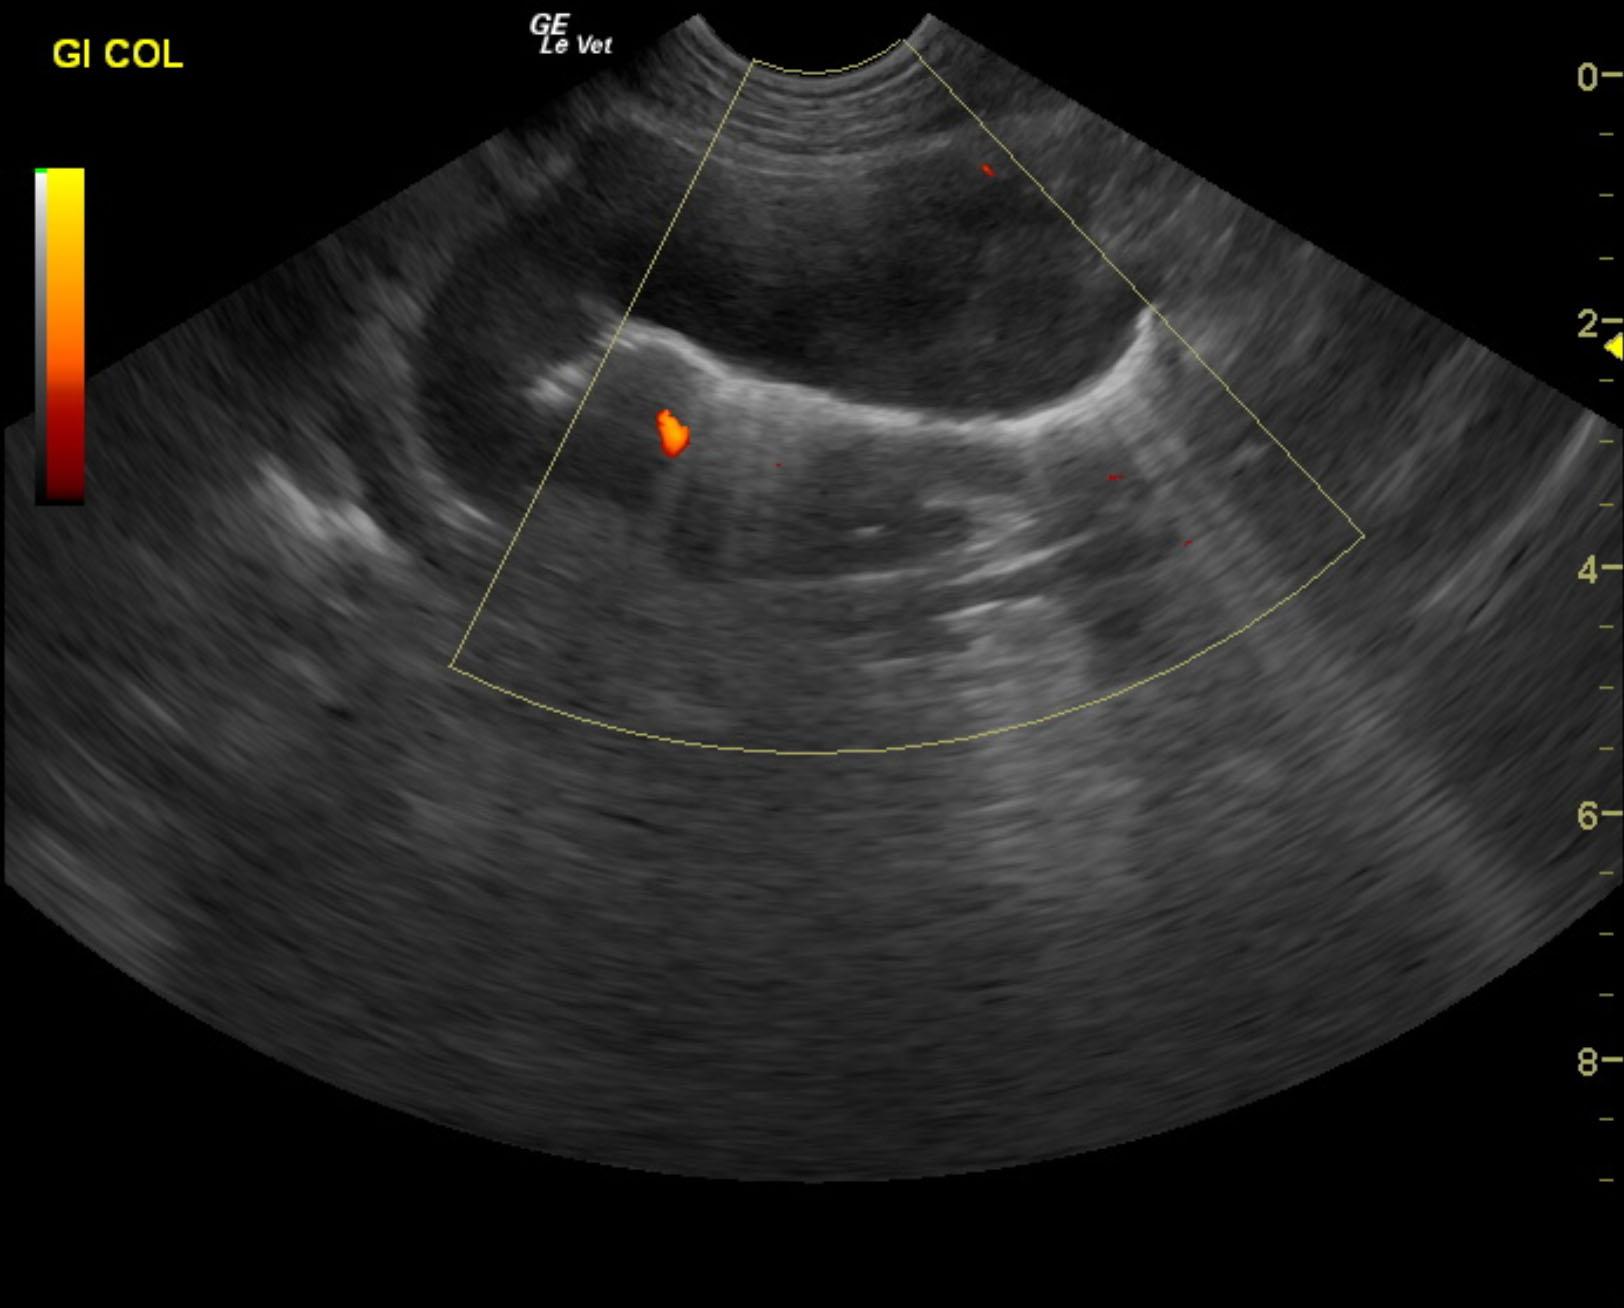

An 8-year-old SF Boxer was presented for evaluation of a one-month duration of vomiting, melena, and anorexia.

The gastrointestinal tract revealed a focal intestinal mass with an infiltrative pattern and loss of detail. The mass measured 3.0 cm in length x 2.5 cm in width. Variable areas of small intestinal thickening were also noted. Separate areas of hypoechoic, infiltrative neoplastic pattern were noted in variable areas of the gastrointestinal tract and the stomach. Reactive fat was noted associated with the variable intestinal infiltrative pattern. The intestinal mass and lymph node were aspirated with ultrasound guidance.

Gastrointestinal lymphoma pattern with regional lymphadenopathy. This is not resectable. Recommend assessment of cytology and chemotherapeutic intervention.